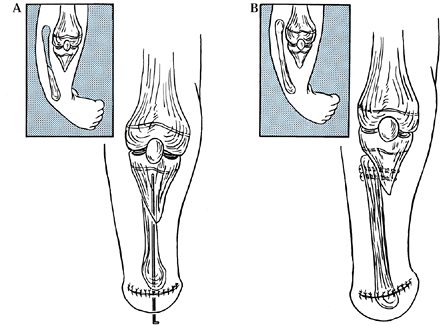

through an anterior approach to the ankle (Fig. 174.5).

Figure 174.5.

The Wiltse osteotomy reduces the medial prominence of the ankle following correction of a residual valgus ankle deformity, as might accompany lesser degrees of fibula deficiency. A: Plan of wedge resection. B: After closure and fixation of the osteotomy. |